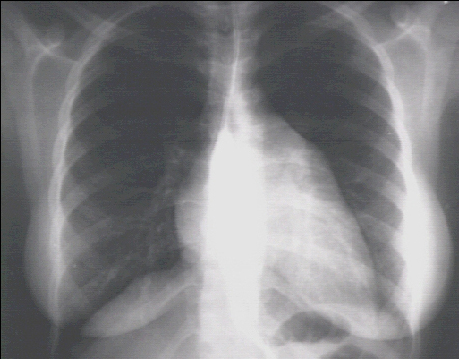

These chest X rays show left ventricular enlargement and left atrial enlargement. This PA view demonstrates the enlarged left ventricle as an increase in the inferolateral cardiac border associated with an increased cardiothoracic ratio. The markedly enlarged left atrium is manifested by the double contour within the heart border, an elevated left mainstem bronchus, and an enlarged left atrial appendage.